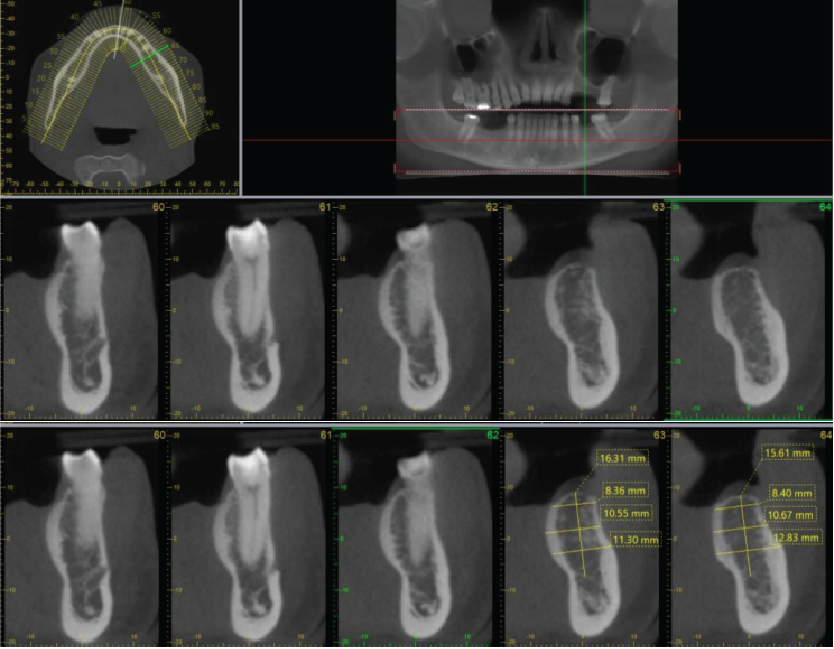

Image 2

Panoramic reconstruction

Periodontal bone levels are mainly normal or show mild bone loss, but there is greater bone loss associated with UR8 and UR7 and incidental finding of caries. UL4, UL5, UL6 sites have a mature alveolar ridge. No retained roots or bony pathosis. Selected images 3 are bucco-palatal cross-sections across the site. Bone height to the antral floor steadily falls moving distally across the site. There is a short transverse septum at the maxillary antral floor above the palatal side of UL5 site, which should not be relevant to any sinus lift procedure being planned. The alveolar bone quality appears satisfactory, with fairly dense trabeculation and well-defined cortices. The LL6 site has a mature alveolar ridge with no retained roots or bony pathothis. LL7 is mesially inclined, so that its crown overhangs the site. Selected images 4 are bucco-lingual cross-sections across the site. The alveolar ridge has a broad crest. There is a mild lingual undercut, with a lingual concavity present mesially in the site and in the premolar region. The lingual concavity of the submandibular fossa appears towards the distal end of the site. The ID canal is easily identified, lying quite low in the bone. The mental canal is in the plane of LL5. Bone quality is satisfactory, with well-defined thick cortices and fairly evenly trabeculated medullary bone.